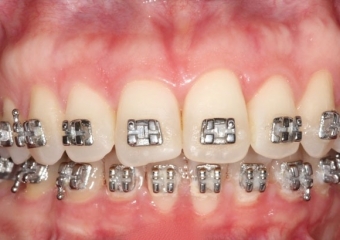

Mordida inicial

Mordida final